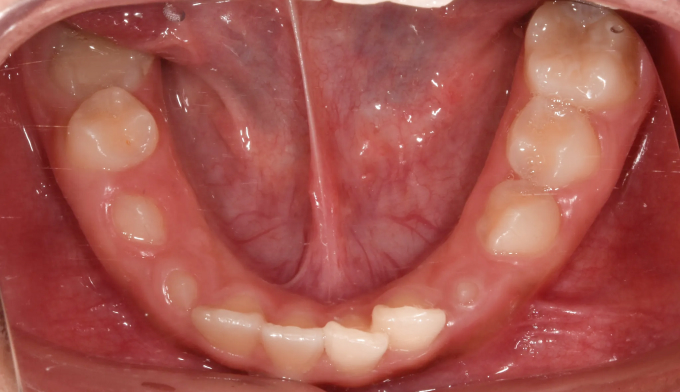

엑스레이를 찍어보니 치아가 나올 공간이 많이 부족하여 이가 고르지 못하고 송곳니가 나올 공간도 부족해 보였습니다. 정상적인 맹출 순서가 어긋나다보니 치열의 비대칭도 관찰됩니다.

약 8개월간의 공간확장치료를 통하여 이가 배열되고 송곳니가 나올 공간을 만들어주었습니다.

공간 확보 후 치아를 배열하여 교정 마무리 하였습니다.